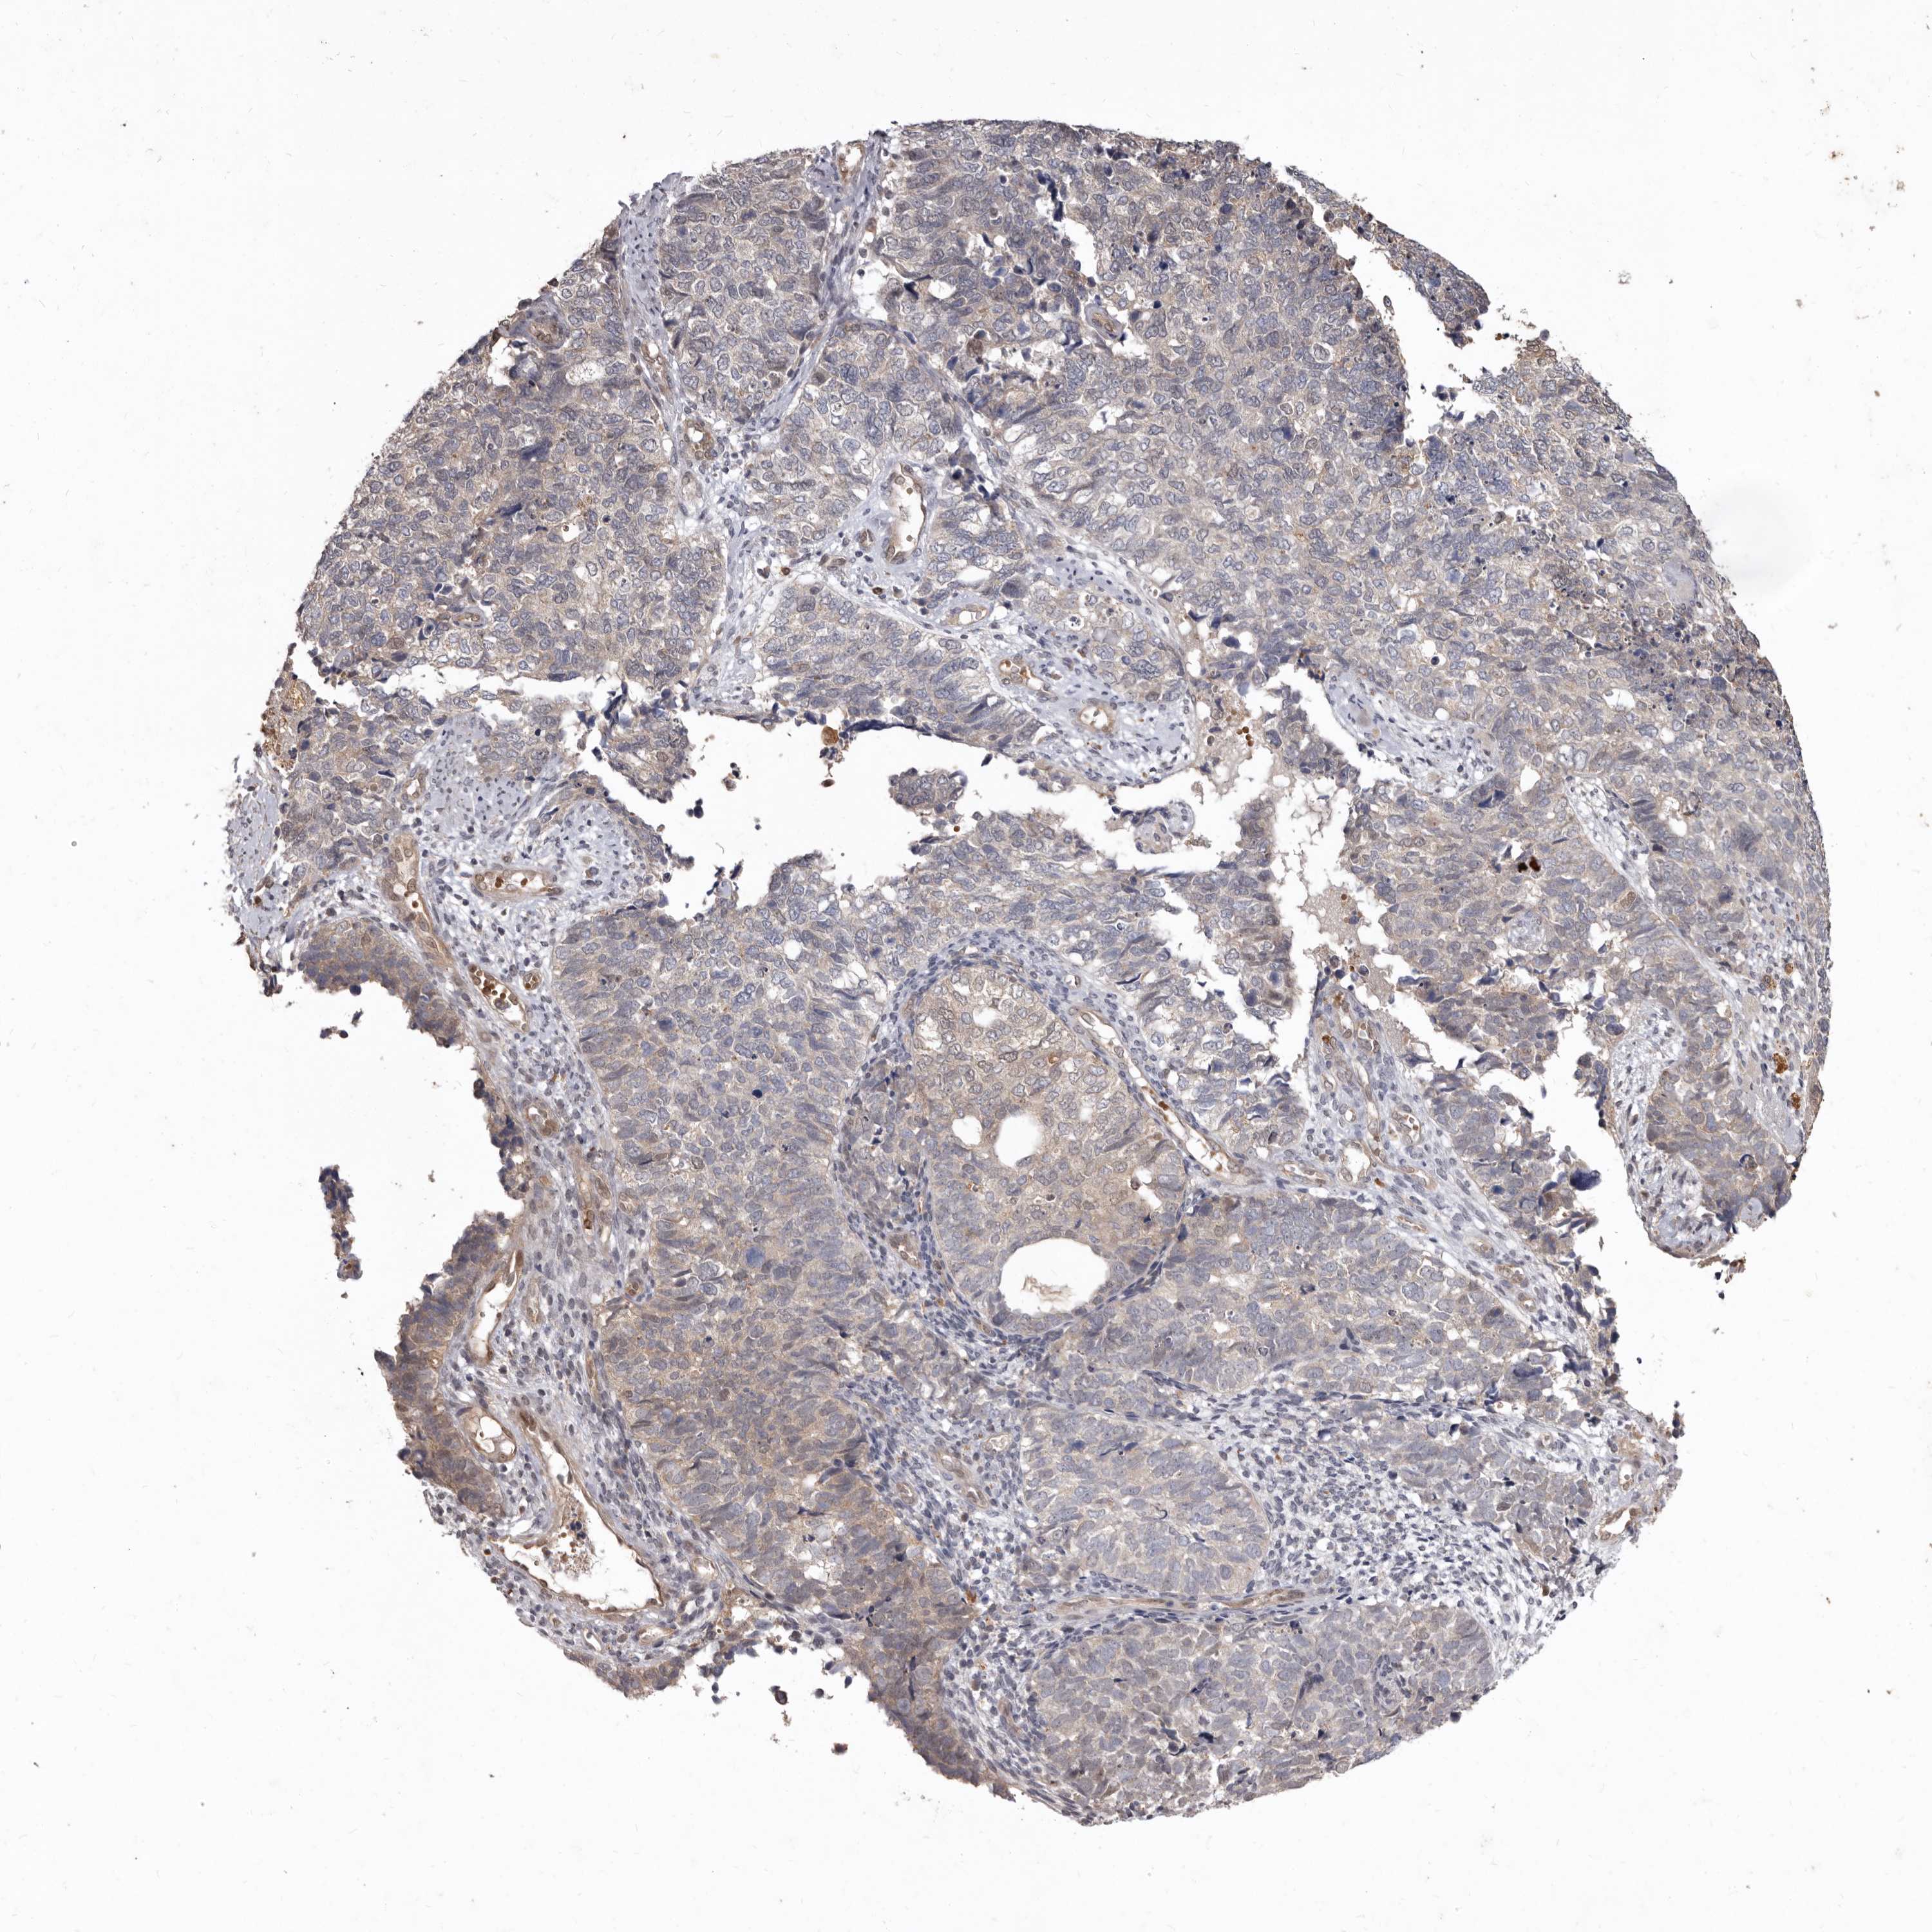

CERVICAL CANCER - Protein expressioni

A mouse-over function shows sample information and annotation data. Click on an image to view it in a full screen mode. Samples can be filtered based on level of antibody staining by selecting one or several of the following categories: high, medium, low and not detected. The assay and annotation is described here.

Note that samples used for immunohistochemistry by the Human Protein Atlas do not correspond to samples in the TCGA dataset.

Antibody stainingi

Antibody staining in the annotated cell types in the current human tissue is reported as not detected, low, medium, or high, based on conventional immunohistochemistry profiling in selected tissues. This score is based on the combination of the staining intensity and fraction of stained cells.

Each image is clickable and will lead to virtual microscopy that enables deeper exploration of all samples and also displays staining intensity scores, fraction scores and subcellular localization as well as patient and tissue information for each sample.

Squamous cell carcinoma, NOS

Adenocarcinoma, NOS